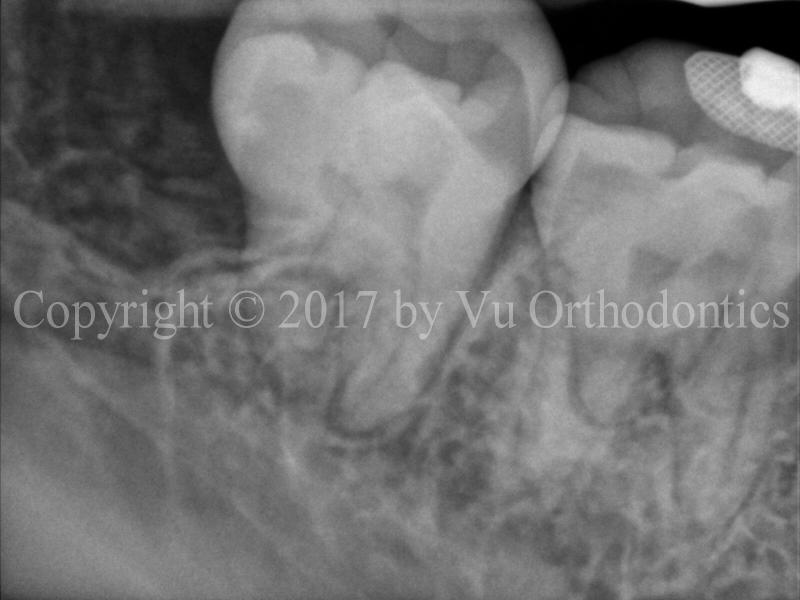

The following example shows a case of an orthodontic patient that needs four premolars extracted. In this case, saving wisdom teeth is the right thing to do. Figure 1 shows an image of impacted wisdom tooth #17.

Fig. 1 Impacted wisdom tooth #17